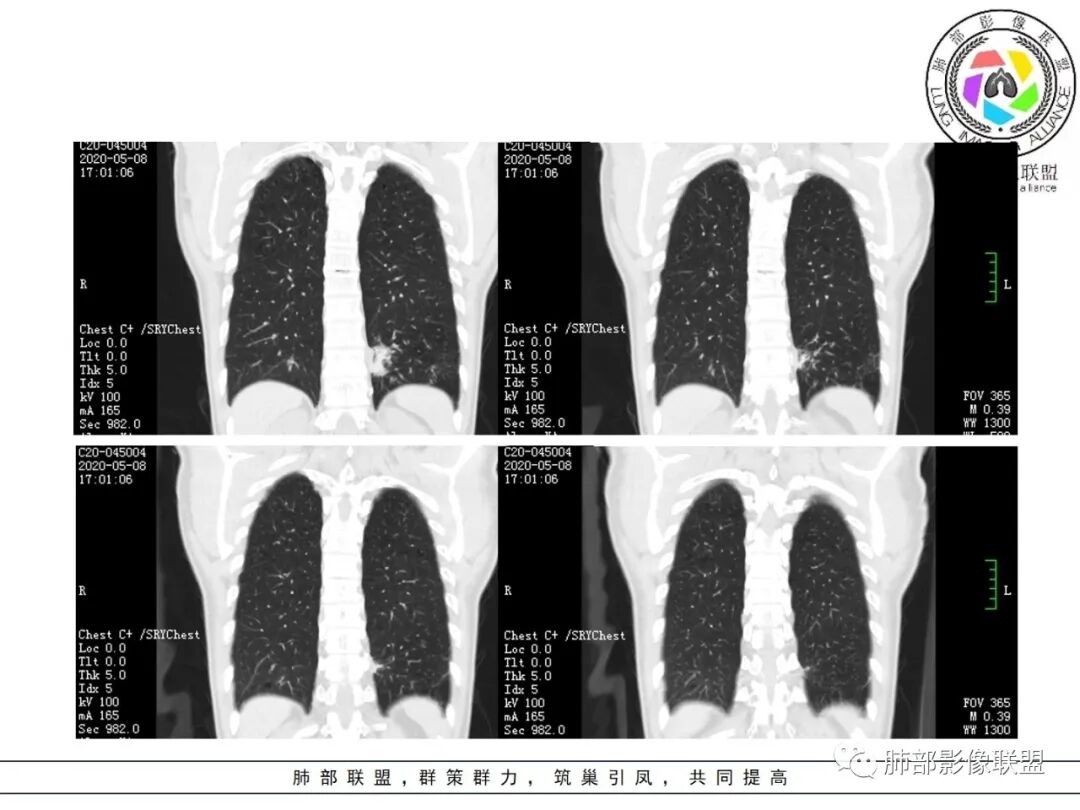

1.关于病灶分布:本例多发小片影局限在左肺下叶,其他肺叶未见异常病灶。

而肺结核表现为多灶性、多形态、多钙化性,本例前述征象均未见到,亦未见结核的典型树芽征。故肺结核缺乏支持点。

2.关于支气管:上述病灶辖区外侧段支气管截断,环壁结节,远端阻塞性肺炎,是肺癌的重要征象。

支气管内膜结核,易导致支气管较长范围壁增厚,管腔不均匀狭窄甚至狭窄后扩张,也会引起远端肺组织相应的改变,如含气不良、液性潴留等,但较少出现树芽征或新旧不等结节影。支气管镜检有助于鉴别。